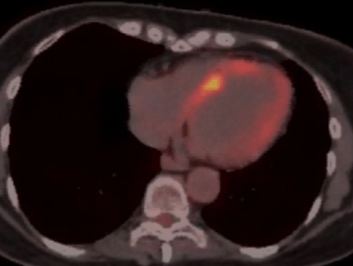

Cardiac sarcoid: A great Masquerader !

A real-life case with a common clinical scenario, where sarcoid can mimic ischaemic heart disease.